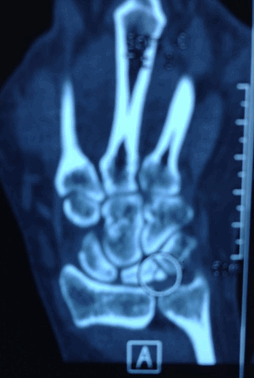

На компьютерной томографии были признаки фрагментации полулунной кости.

Пациентка 26 лет пришла на прием с болью в запястье. До нашей встречи жалобы были уже больше полугода. К моменту осмотра болезнь Кинбека была уже диагностирована, разрушение полулунной кости отчетливо видно на рентгене, стадия 3б.

МРТ и КТ являются наиболее чувствительными при диагностике болезни Кинбека; простая рентгенография показывают отклонения позже, как правило, при начале склеротических изменений полулунной кости, сменяющихся кистозными изменениями, фрагментацией и коллапсом.

В диагностике болезни Кинбека используются рентген, МРТ и КТ. МРТ особенно важна для определения стадии заболевания, а рентген позволяет выявить отек костей, который плохо наблюдается на первых стадиях заболевания. Раннюю диагностику и вмешательства желательно осуществлять с помощью визуализации на устройстве МРТ 3 Тесла. С помощью томографии оценивают перелом и коллапс кости и возможные истирания вокруг полулунной кости и запястья в целом.